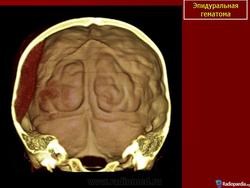

2. КТ головного мозга, демонстрирующее редкий случай эпидуральной гематомы снования черепа (указано стрелкой)

3. Эпидуральная гематома основания черепа в области перелома задней черепной ямки (указано стрелками)